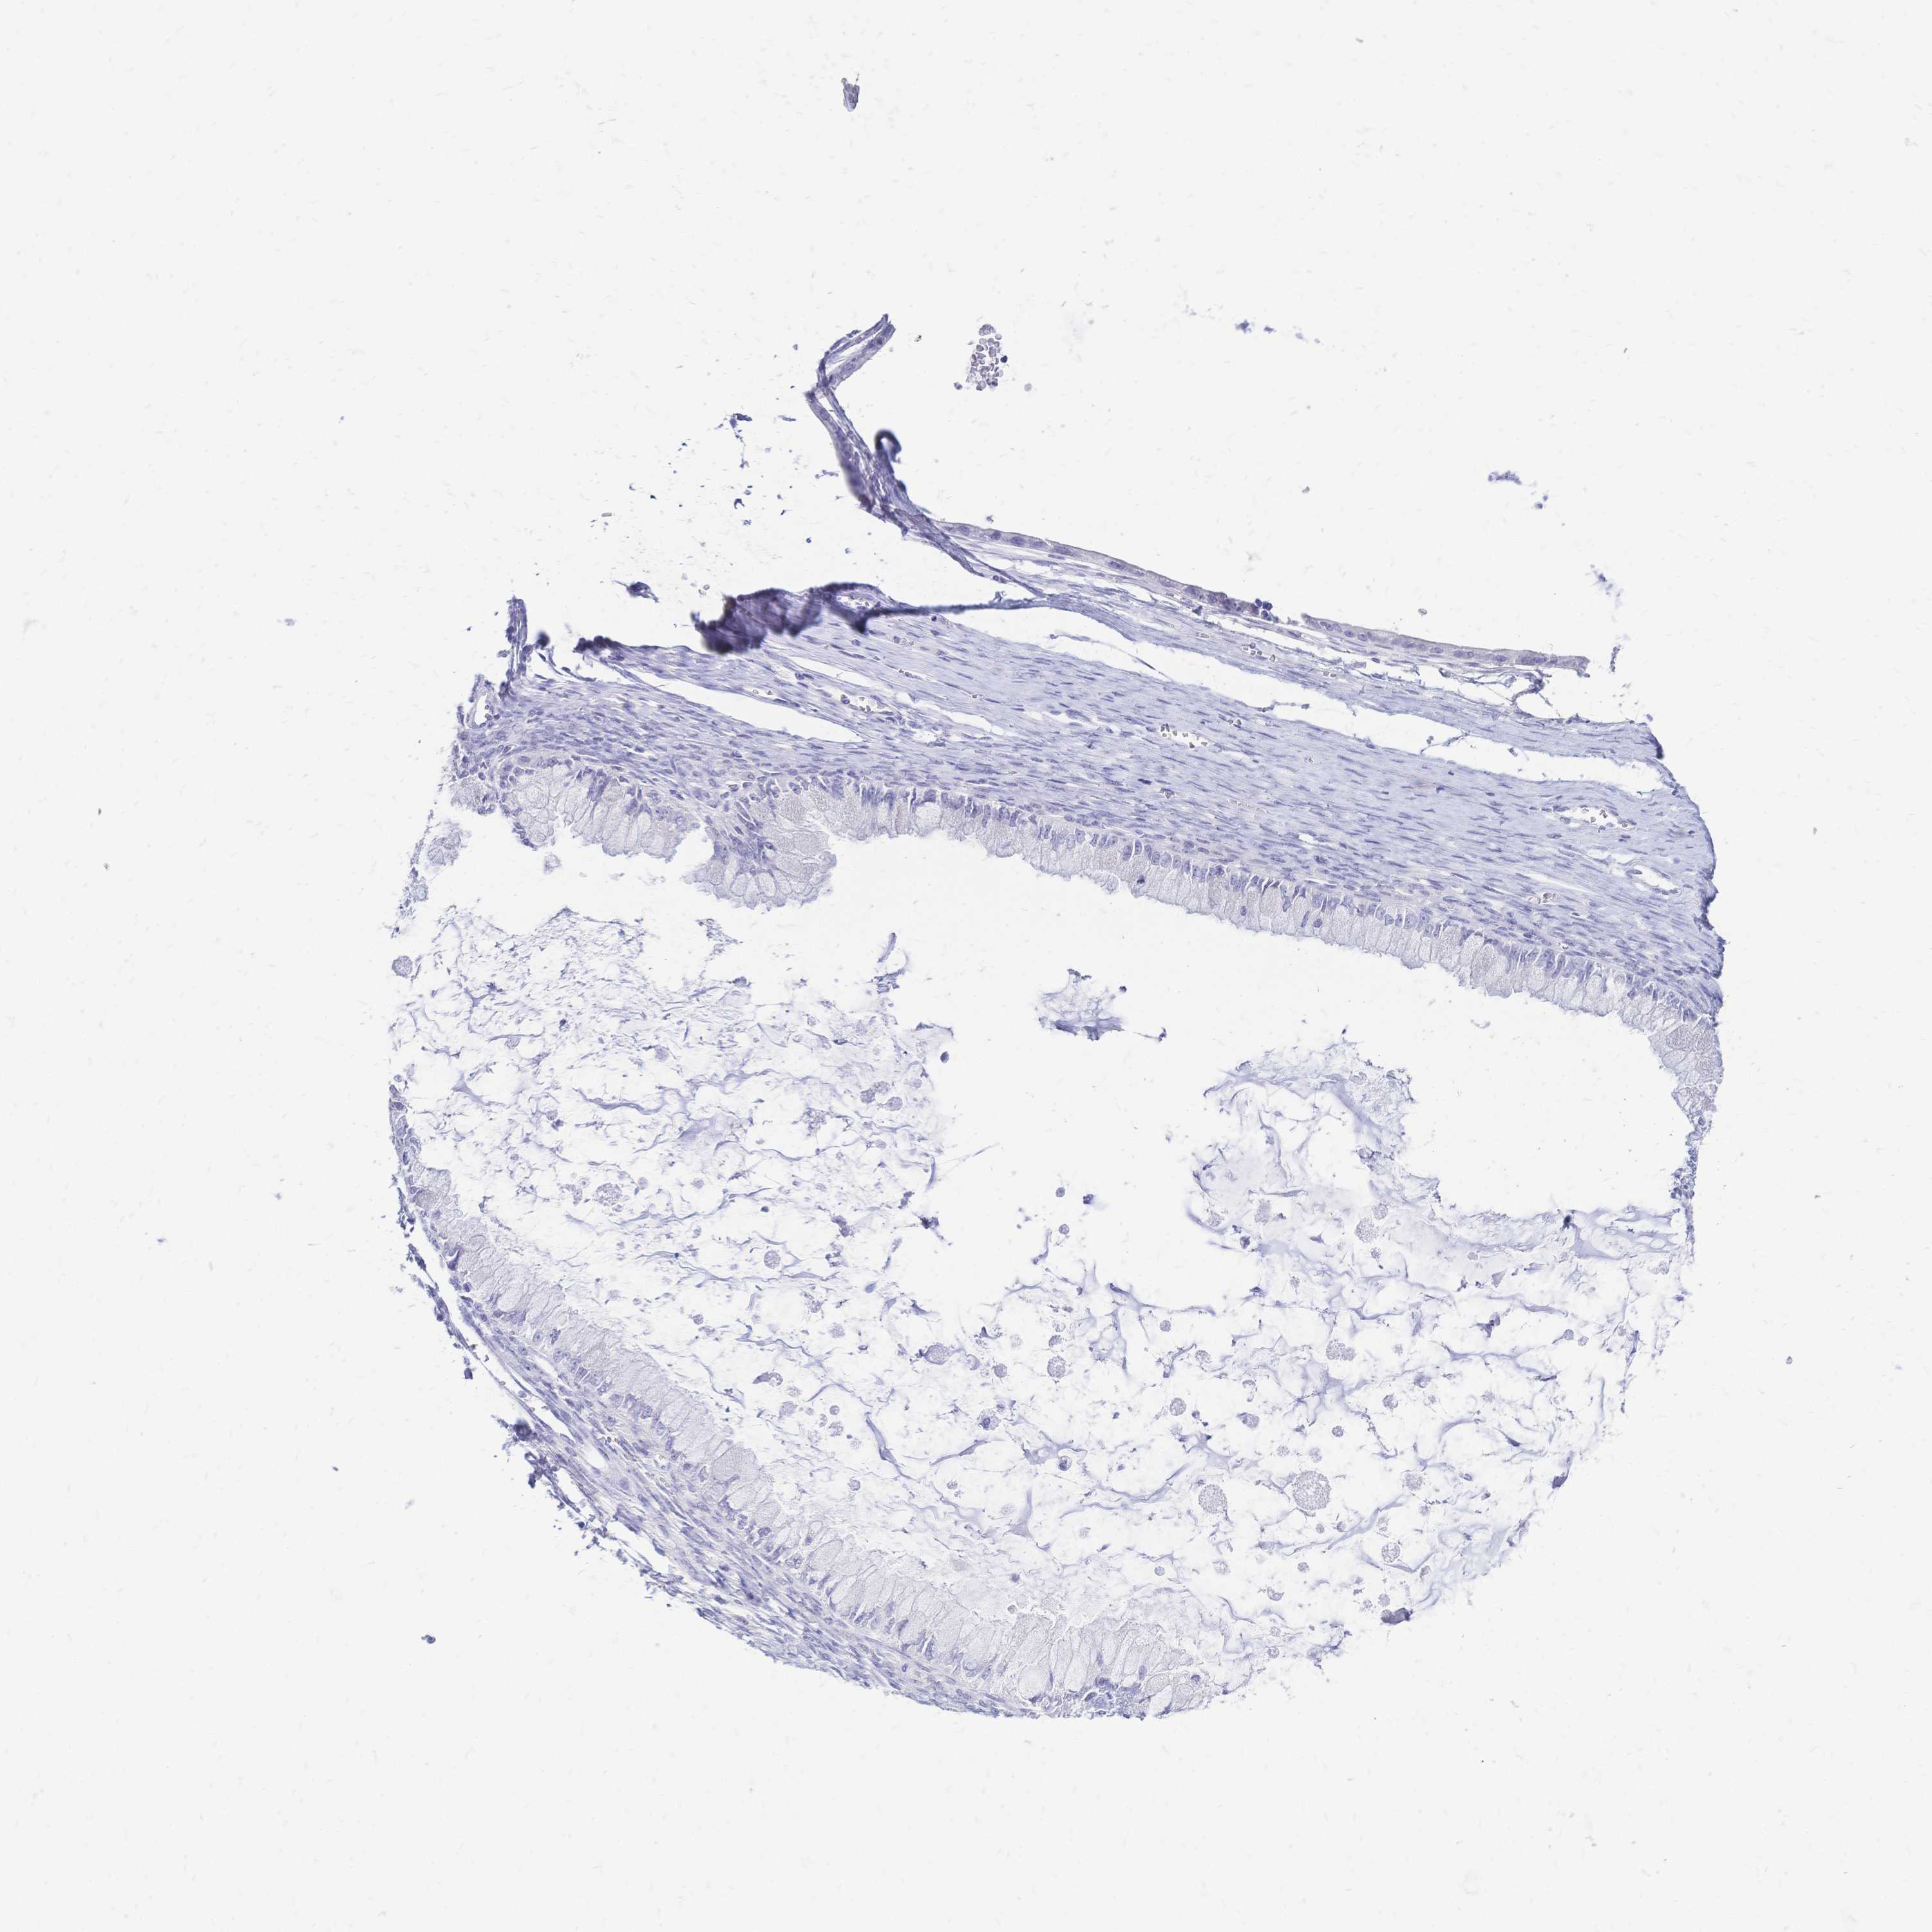

OVARIAN CANCER - Protein expressioni

A mouse-over function shows sample information and annotation data. Click on an image to view it in a full screen mode. Samples can be filtered based on level of antibody staining by selecting one or several of the following categories: high, medium, low and not detected. The assay and annotation is described here.

Note that samples used for immunohistochemistry by the Human Protein Atlas do not correspond to samples in the TCGA dataset.

Antibody stainingi

Antibody staining in the annotated cell types in the current human tissue is reported as not detected, low, medium, or high, based on conventional immunohistochemistry profiling in selected tissues. This score is based on the combination of the staining intensity and fraction of stained cells.

Each image is clickable and will lead to virtual microscopy that enables deeper exploration of all samples and also displays staining intensity scores, fraction scores and subcellular localization as well as patient and tissue information for each sample.

Antibody HPA056614

Staining

High

Medium

Low

Not detected

Intensity

Strong

Moderate

Weak

Negative

Quantity

>75%

75%-25%

<25%

None

Location

Nuclear

Cytoplasmic/membranous

Cytoplasmic/membranous,nuclear

Cystadenocarcinoma, serous, NOS

Cystadenocarcinoma, mucinous, NOS

Carcinoma, endometroid